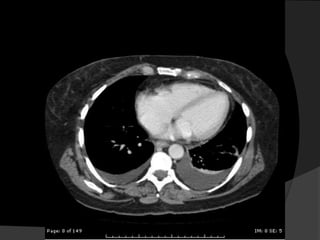

Avaliação Inicial

 Estudos ultra-sonográficos

 Radiografias em decúbito lateral

(Laurel)

 Tomografia Computadorizada (TC) para

analisar o parênquima pulmonar

subjacente ou mediastino.